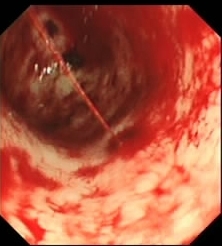

急性上消化道出血是常見的急症,有可能導致死亡,在香港每年每十萬位成人約有130名患者。上消化道出血最常見的原因是消化性潰瘍,佔報告病例的35-50%。 上消化道出血的其他相關病因包括:胃十二指腸糜爛(8-15%),食道炎(5-15%),靜脈曲張(5-10%),食道裂傷(15%),和血管畸形(5%)。 上消化道出血的症狀有吐出鮮血、咖啡色的嘔吐物及排出黑色大便。 嚴重時,可能會導致死亡。